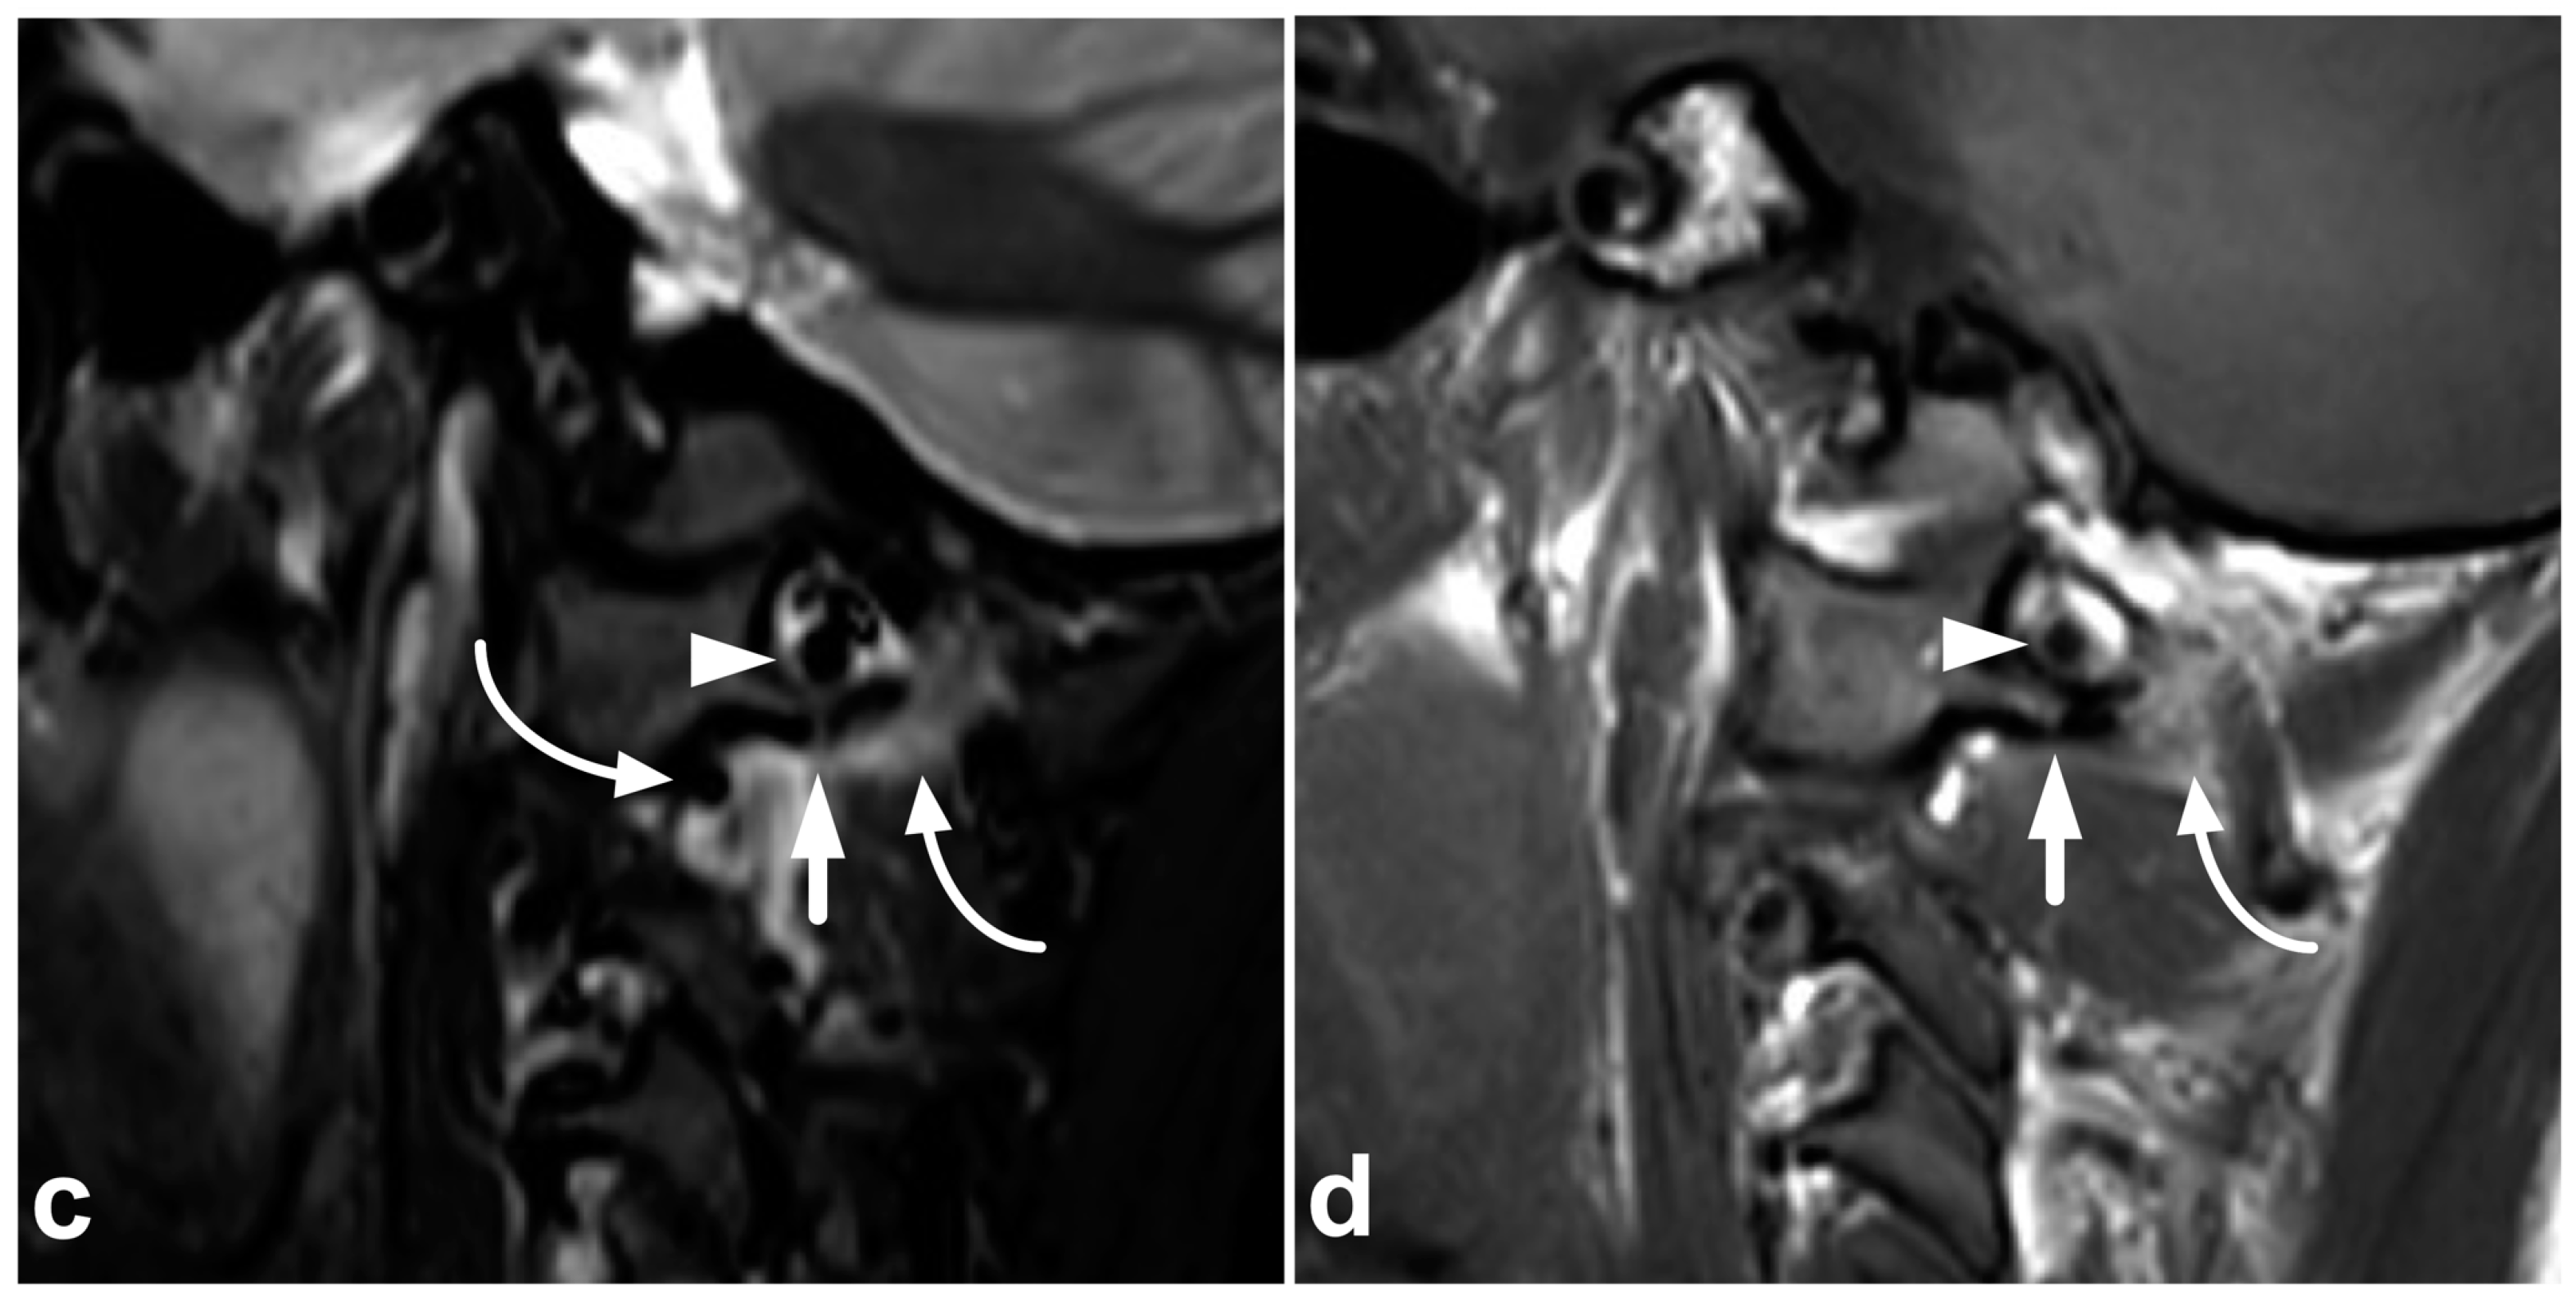

4.1. Occipitocervical and Atlantoaxial Ligaments